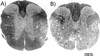

Following intracerebral infection with Theiler's murine encephalomyelitis virus (TMEV), susceptible strains of mice (SJL and PLJ) develop virus persistence and demyelination similar to that found in human multiple sclerosis. Resistant strains of mice (C57BL/6) clear virus and do not develop demyelination. To resolve the controversy about the role of CD4(+) and CD8(+) T cells in the development of demyelination and neurologic deficits in diseases of the central nervous system, we analyzed TMEV infection in CD4- and CD8-deficient B6, PLJ, and SJL mice. Genetic deletion of either CD4 or CD8 from resistant B6 mice resulted in viral persistence and demyelination during the chronic stage of disease. Viral persistence and demyelination were detected in all strains of susceptible background. Although genetic deletion of CD8 had no effect on the extent of demyelination in susceptible strains, deletion of CD4 dramatically increased the degree of demyelination observed. Whereas strains with deletions of CD4 showed severe neurologic deficits, mice with deletions of CD8 showed minimal or no deficits despite demyelination. In all strains, deletion of CD4 but not CD8 resulted in a decreased delayed-type hypersensitivity response to viral antigen. We conclude that each T-cell subset makes a discrete and nonredundant contribution to protection from viral persistence and demyelination in resistant strains. In contrast, in susceptible strains, CD8(+) T cells do not provide protection against chronic demyelinating disease. Furthermore, in persistent TMEV infection of the central nervous system, neurologic deficits appear to result either from the absence of a protective class II-restricted immune response or from the presence of a pathogenic class I-restricted response.